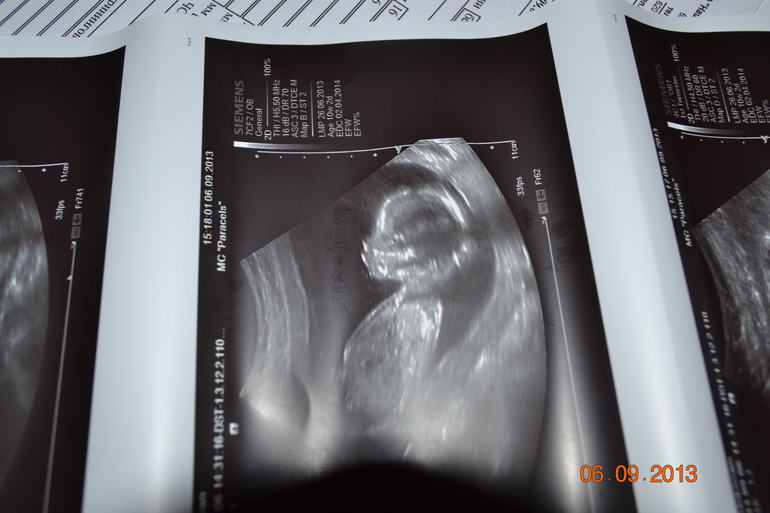

Результаты: УЗИ, КТГ, доплера, скринингаНачался день с крови (писала уже, что как стала ставить свечи Гексикон, стало кровить), но это были уже далеко не капельки как первые дни. Подумала, что пошли они на...ставить больше не буду. Но на работе обнаружила, что кровить продолжает и достаточно активно. Позвонила в женскую: - вызывайте скорую, либо сразу в стационар приезжайте. Девочки, не подумайте, не против перестраховаться, но ложиться на выходные сами знаете, врача все равно нет, выпустят неизвестно когда, а у нас свадьба на следующей неделе. Гиня как вариант предложила схожить на УЗИ (куда-нить), убедиться что угрозы нет. Начала искать, все по записи, либо делают только скрининги. Обзвонила центров 10, наверное, начала нервничать, заболел живот, нервозность перешла в панику, мозг в отключку, слезы ручьем. Нашли дорогущий центр, пофиг, понеслись, ситуацию обрисовали, начали смотреть Уф, никаких угроз она не нашла, тонуса нет, сокращений нет, шейка в норме, отслойки нет, признаков маточного кровотечения нет. В общем все-таки эрозия так на свечи среагировала. Ну все, как успокоились все, начали нам всё внимательно показывать и....у нас ДЕВОЧКА. Полюбуйтесь на нашу принцесску

. Папа в шоке, что он с нами делать будет)))